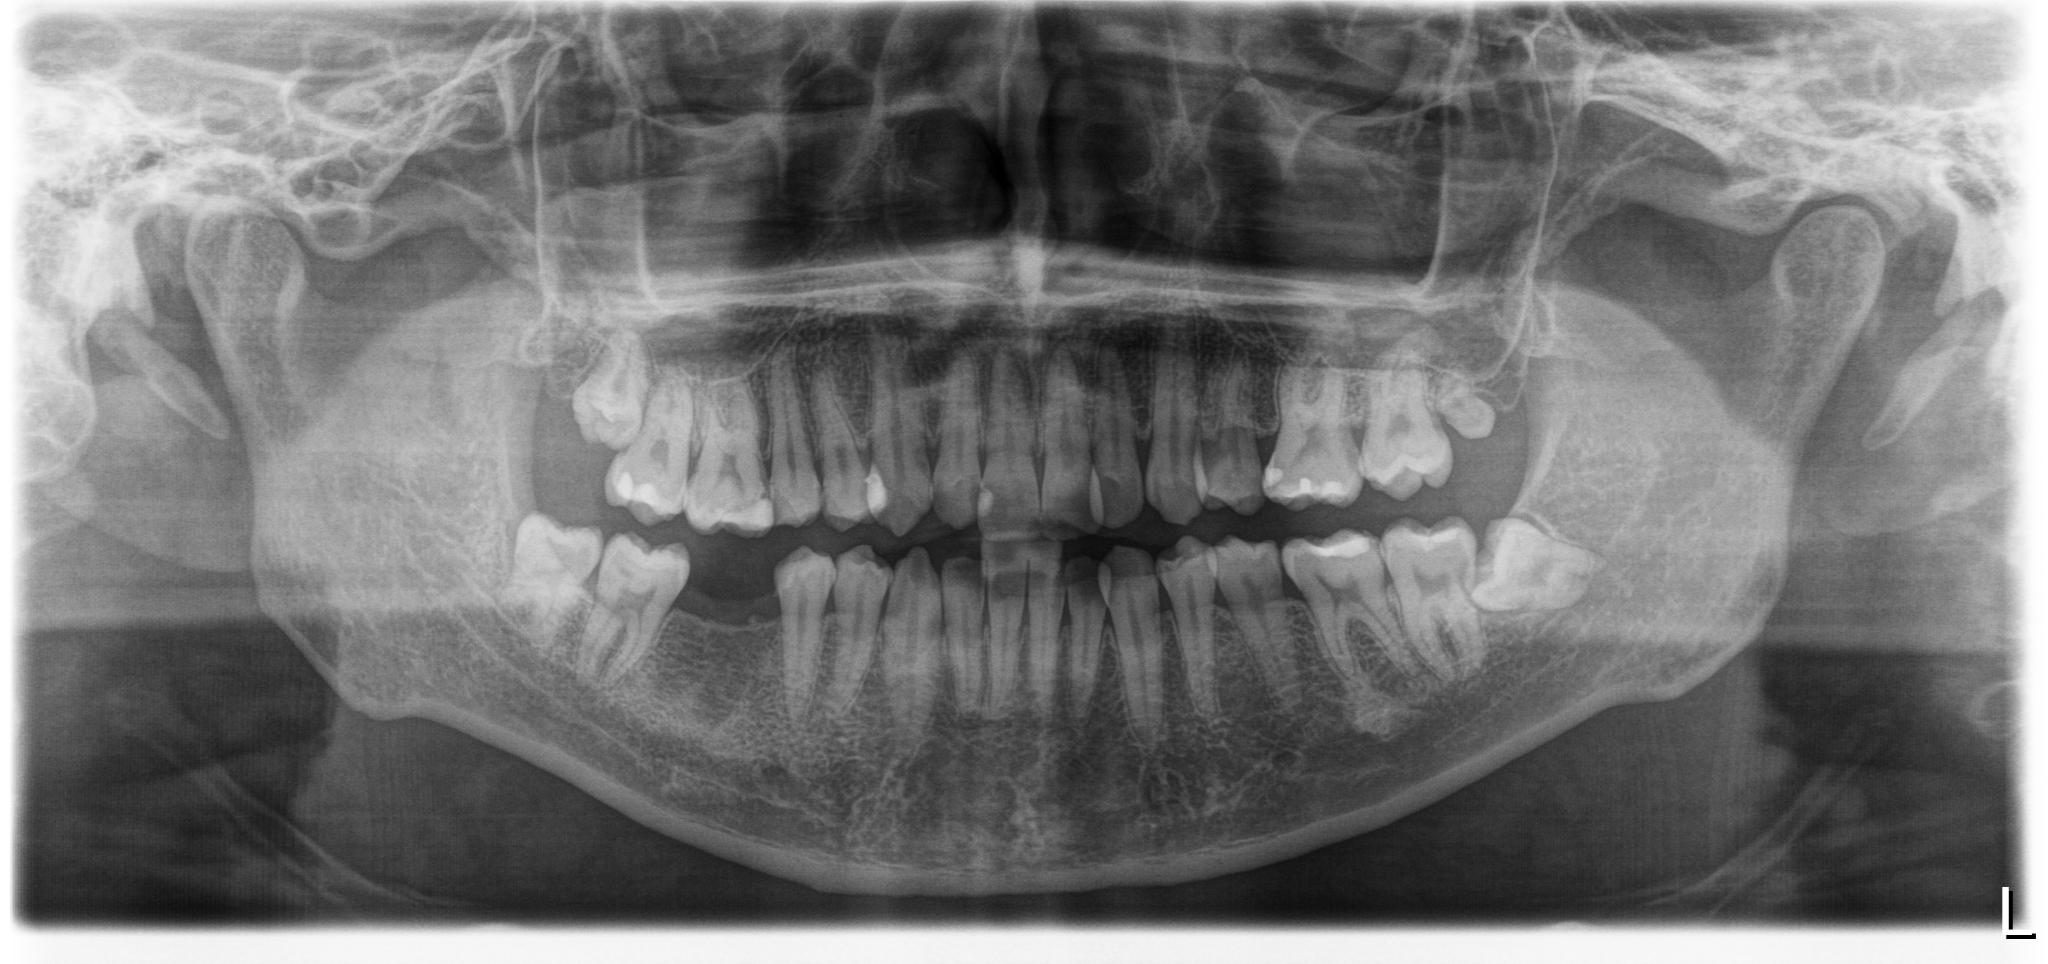

治療前レントゲン画像

治療後レントゲン画像

| 主訴 | 右下奥の治療方法の相談をしたい |

|---|---|

| 年齢 | 初診時:26歳 |

| 性別 | 男性 |

| 治療内容 | 右下6番 インプラント埋入術 |

| 治療期間 | 約6ヶ月 |

| 治療費用 |

562,000円(税込) |

| リスク、副作用 | 術後疼痛、腫脹、出血、下口唇の感覚異常 |